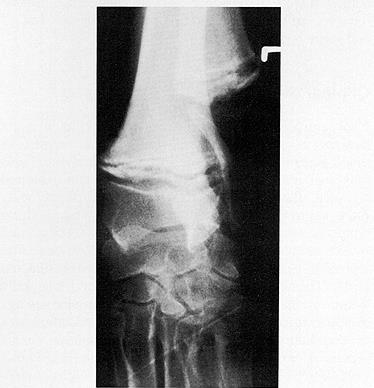

5个月大的肥大性骨营养不良的大丹犬尺骨X光片

X光线通常显示病变骨头的变化,例如与生长板平行线的外观,骨密度的变化以及生长板周围的钙化。